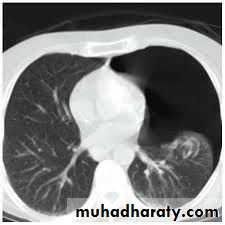

CoagulopathyPulmonary bullae

Fall from the 2nd floor